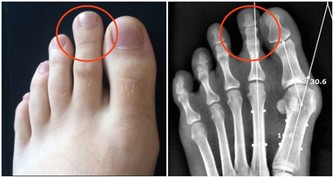

超聲科醫師檢查發現其右側陰囊空虛,右側腹股溝內可見大小約2*2*1cm的類睾丸迴聲,診斷考慮:隱睾症。

超聲科劉友員主任醫師解釋,“蛋蛋”不在陰囊裡就是俗稱的“隱睾症”。

隱睾,是指睾丸在正常發育過程中未下降或下降不全至陰囊,陰囊內沒有睾丸或只有一側有睾丸。